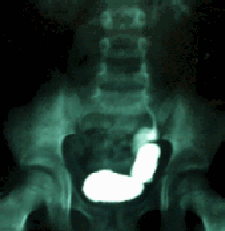

Figura 1. Divertículo vesical con reflujo.

La Figura 1 muestra un enorme divertículo vesical con reflujo de bajo grado. Suponemos que la lesión inicial fue el divertículo que en su progresivo crecimiento, desplazó al uréter de su soporte muscular. El niño consultó a los 4 años de edad luego de la primera infección urinaria y ya existía una cicatriz renal. ¿Qué papel jugó la infección?